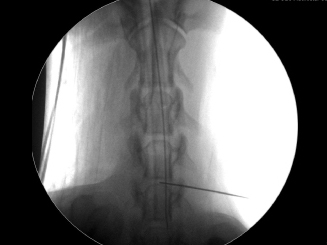

【診療科目】>神経科> 経皮的レーザー椎間板減圧術(PLDD)

椎間板ヘルニアの治療の中でも「体に負担が少ない」「傷口もほとんど残らない」がPLDD(Percutaneous Laser Disc Decompression)というレーザーによるヘルニア手術です。

傷はほとんどわかりません。Hansen2型に有効。